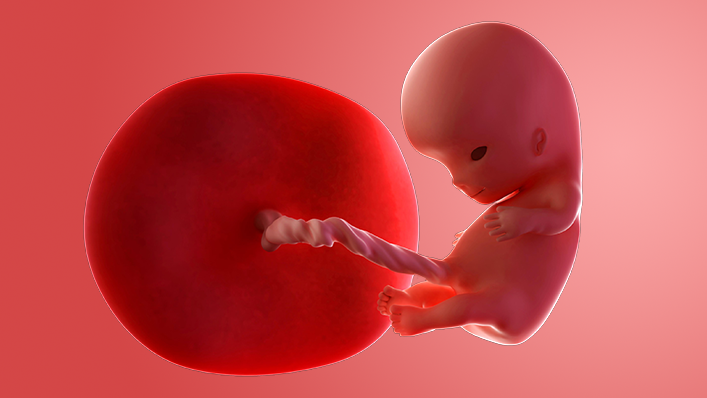

What does my baby look like?

Your baby, or foetus, is now around 41mm long from head to bottom, which is about the size of a fig. The head is still supersized, but the body is growing quickly.

The fingers and toes are separating out. There are tiny fingernails and miniature ears.

Although your baby is kicking around inside your womb, you probably won't feel anything for several weeks.